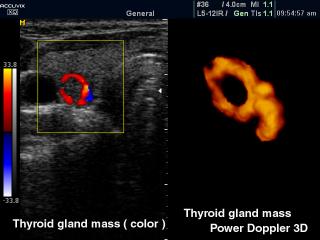

Узел щитовидной железы, ЦДК и энергетический допплер в 3D

Accuvix-XQ. Узел щитовидной железы, ЦДК и энергетический допплер в 3D.